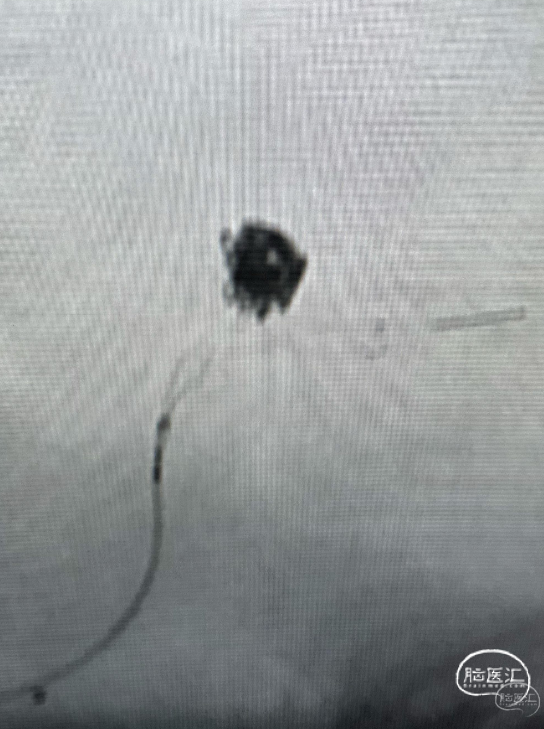

第五台是小脑动静脉畸形。

Glubran胶栓塞。

栓塞后畸形基本不显影。